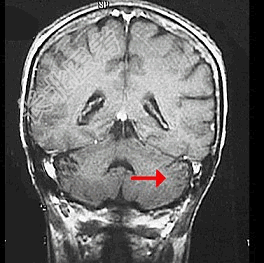

- 单项选择题如图箭头所示,应属于大脑的哪个部位 ( )

A、脑干

B、额叶

C、枕叶

D、小脑

E、顶叶